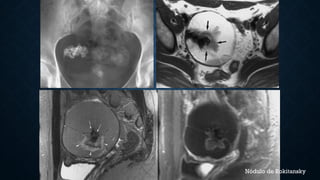

Nódulo de Rokitansky

Mature teratoma.  US imagedemonstrates a mostly echogenic mass (arrows) with areas of sound attenuation. CT scan shows a cystic tumor with fat and calcification (arrows).